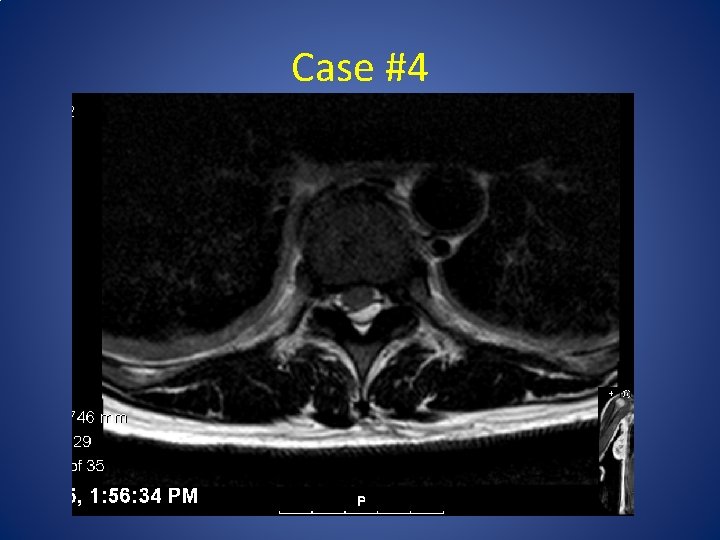

Case #4 • 50 yo female, IV drug user • To ER with fever, severe back pain x 5 days • No numbness, weakness, bowel/bladder dysfunction • III/VI Systolic Ejection Murmur • MRI Spine Done:

Case #4

Case #4 • MRI Spine: Extensive epidural abscess C 5 -L 2, mild cord compression but no cord enhancement • Does this patient need urgent surgical decompression?

Spinal Epidural Abscess • Most often begins as discitis at focal level • Once infection spreads to epidural space can spread longitudinally • >50% caused by Staph aureus – GNB, Strep, anaerobes – Ceftriaxone +/- Vanco +/- Flagyl • MRI test of choice – Better for soft tissues and spinal cord